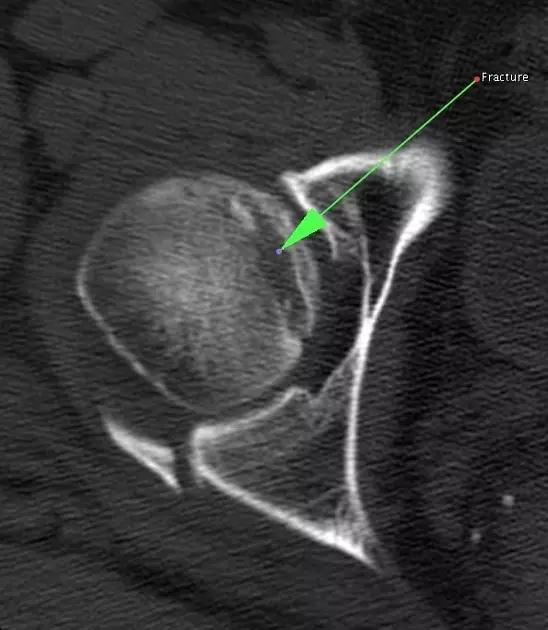

Cedell 骨折的 CT 片 (来源:Fracture of the posterior medial tubercle of the talus :A case report and review of the literature. Acta Orthop. Belg., 2007, 73, 804-806)